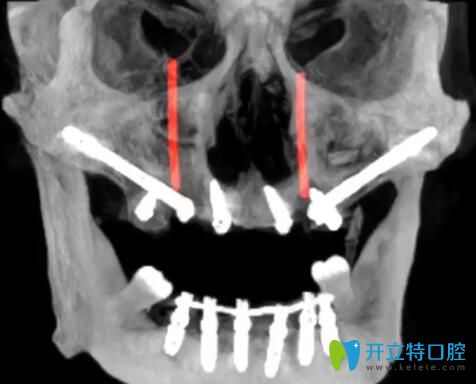

1、TPP穿翼板種植技術(shù)——牙槽骨條件差也能1天種好牙

大家知道種牙的必要條件就是有足量的牙槽骨,針對(duì)牙槽骨萎縮的人群,傳統(tǒng)的種植方法是骨增量,過(guò)程相對(duì)復(fù)雜,而且需要1年的恢復(fù)期。而黎強(qiáng)醫(yī)生的TPP穿翼板種植技術(shù),避開(kāi)血管,把種植體種在牙齒與咽喉交界附近的十分堅(jiān)硬的“翼狀板骨”上,將傳統(tǒng)種植1年才能解決的問(wèn)題,在1天內(nèi)種好牙,且遠(yuǎn)期效果好。

2、數(shù)字化導(dǎo)板導(dǎo)航種植技術(shù)—— 精準(zhǔn)種牙“毫厘不差”

缺牙時(shí)間過(guò)長(zhǎng)不種牙,鄰牙就會(huì)向缺牙處歪斜,種植難度加大,而借助3D數(shù)字化導(dǎo)板,精準(zhǔn)定位植體部位,大大提高了精準(zhǔn)度,普通種植牙需翻瓣切開(kāi)手術(shù)并縫合,數(shù)字化導(dǎo)板導(dǎo)航種植技術(shù)無(wú)需翻瓣,縮小了出血量。